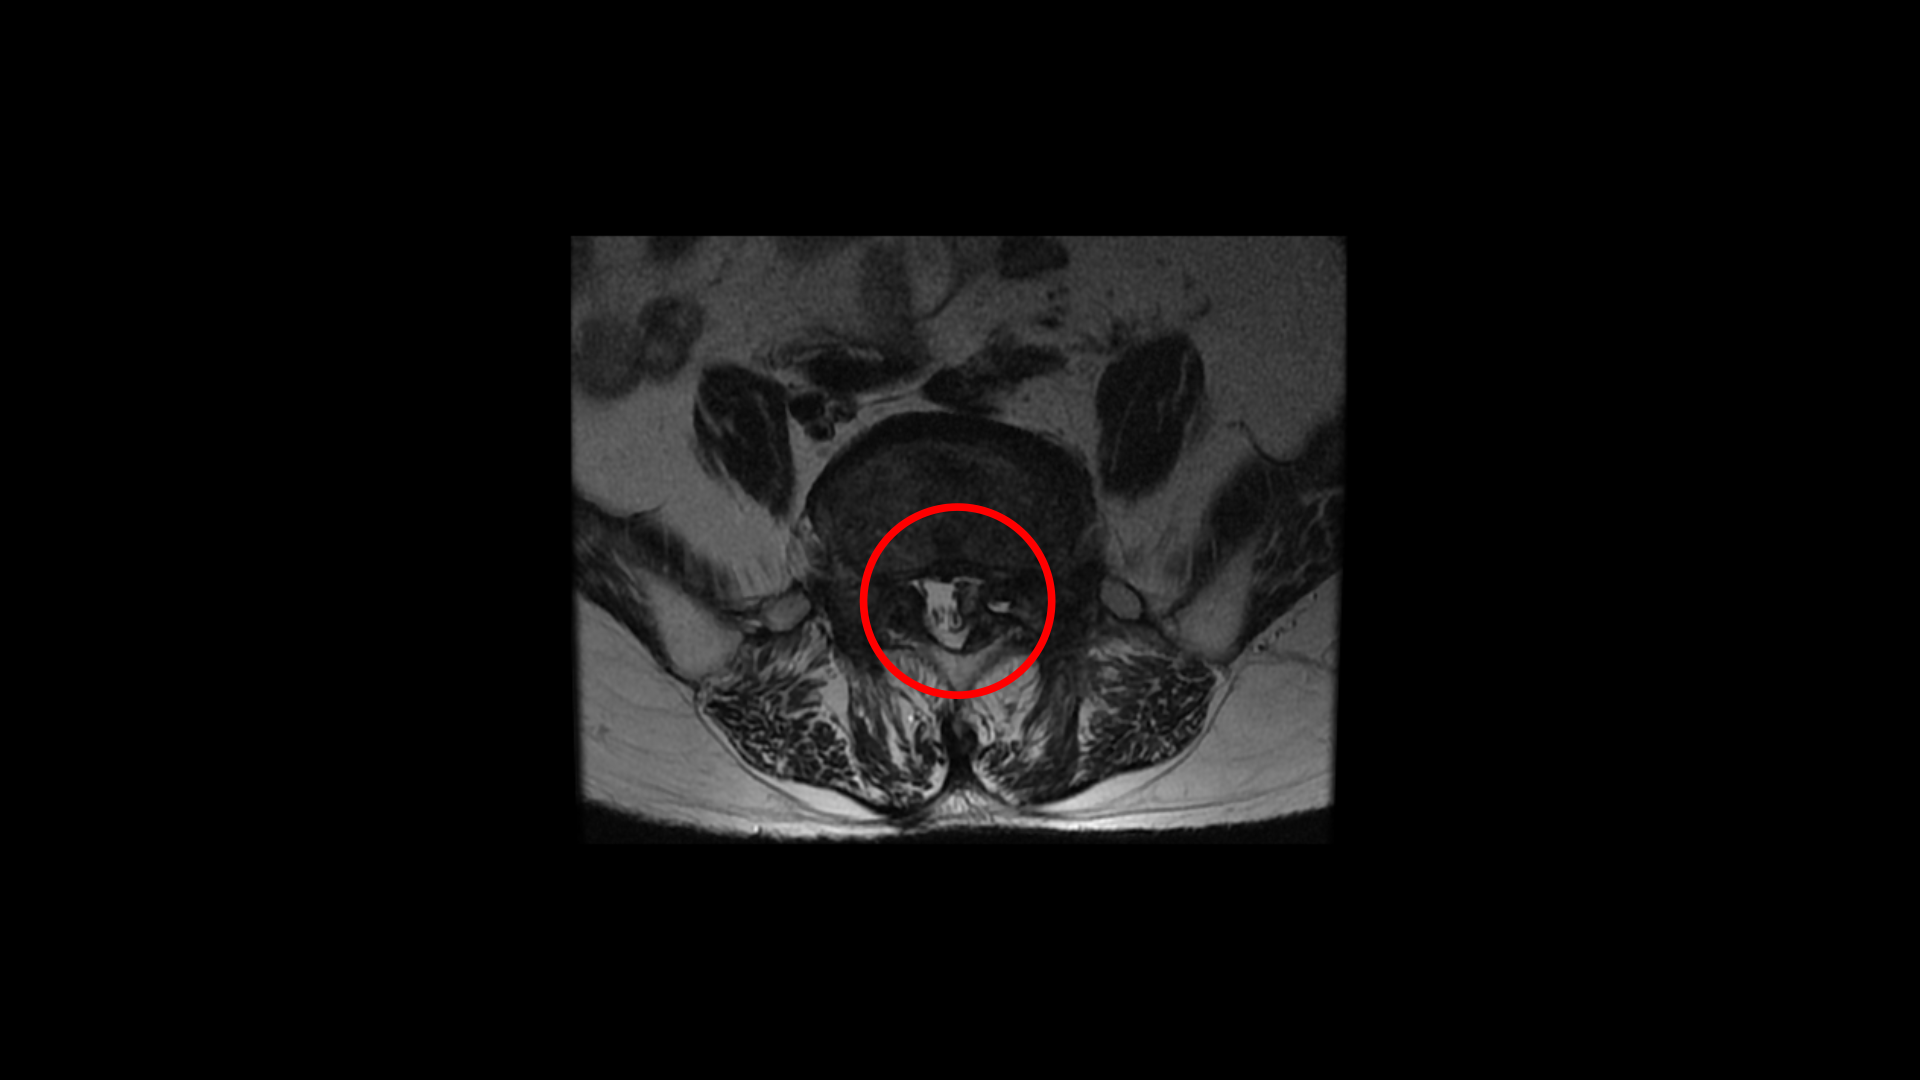

이분 MRI를 보면 퇴행성디스크가 여러 마디가 있고 그 중에서도 특히 5번 1번에는

전방전위증과 함께 2번의 수술로 인해 척추관 내부가 지저분해 보이고

또 오른쪽과 왼쪽으로 나가는 신경 구멍이 많이 좁아져 있습니다.